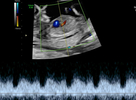

In der Regel wird für diese Untersuchung eine Überweisung vom betreuenden Frauenarzt ausgestellt, z. B. wenn im Rahmen der üblichen in den Mutterschaftsrichtlinien empfohlenen Ultraschalluntersuchung eine Auffälligkeit gesehen wurde. Weitere Gründe für eine Überweisung sind Risikoschwangerschaften oder auch der Wunsch der Eltern nach einer zusätzlichen Absicherung. Neben der allgemeinen Entwicklung des Kindes können hier –noch genauer als im Ersttrimesterscreening – alle Organe des ungeborenen Kindes begutachtet werden. Zusätzlich wird mittels Dopplersonographie die kindliche Versorgung und die des Mutterkuchens überprüft. Da Herzfehlbildungen zu den häufigsten angeborenen Fehlbildungen gehören, stellt die detaillierte fetale Echokardiographie (Untersuchung des kindlichen Herzens) einen wichtigen Bestandteil der Untersuchung dar. Dabei werden sowohl die Anatomie des Herzens als auch die Blutflüsse begutachtet.

Echokardiografie